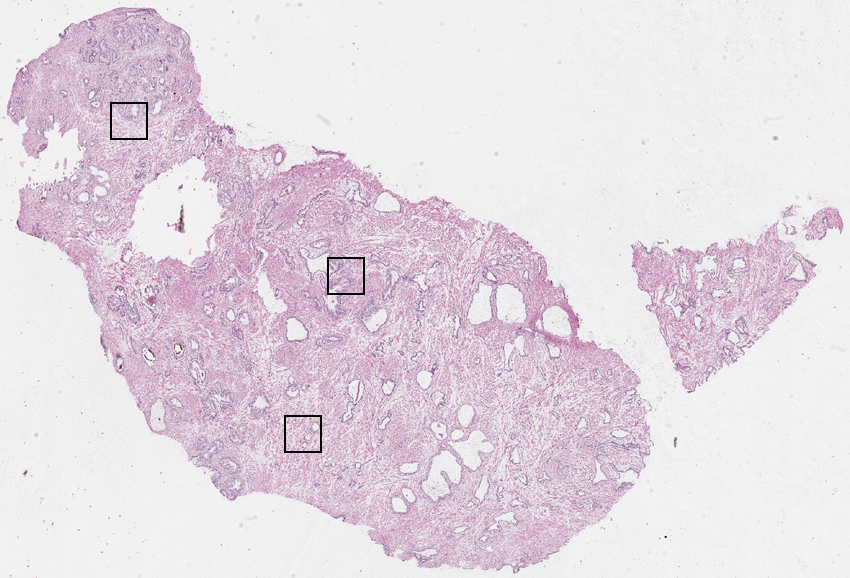

Glandular cells:

40

Smooth muscle cells:

55

Other cell types:

5